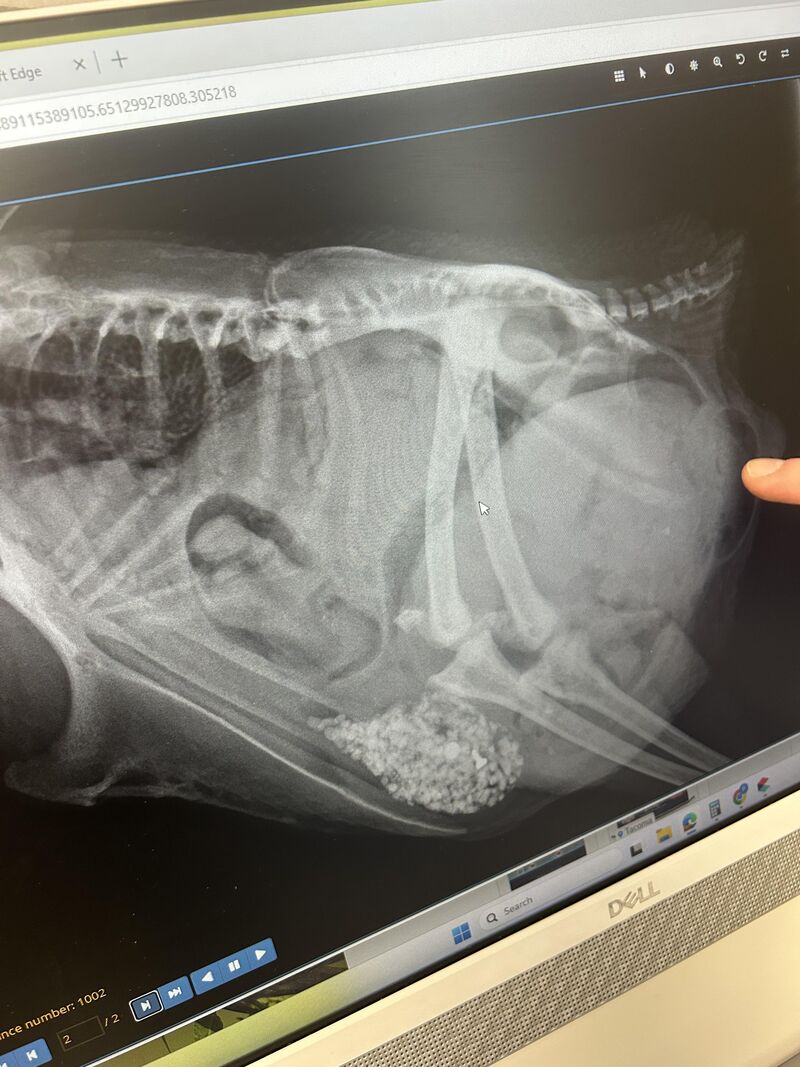

Winnie was euthanized today

Posted by u/allison_vegas in r/BackYardChickens

View on Reddit (1 upvotes)